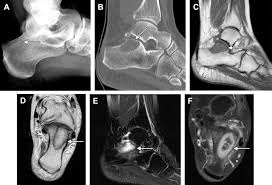

The majority of bone tumors are noncancerous. Bone cancer can weaken the bone it's in, but most of the time the bones do not fracture (break). When examining an mri, an orthopedist will typically look for the following structures, which may indicate osteoarthritis: Osteosarcoma, the most common bone cancer, usually happens to people ages 10 to 30 and most often starts in the arms, legs, or pelvis. Keep friends and family close.

Dog Toe Xray Bone Cancer Or Infection Ask A Vet from www.askavetquestion.com Squamous cell carcinoma is the most common form of cancer on the skin of the feet. Sometimes, people with bone sarcoma do not have any of these changes. Pain caused by bone cancer usually begins with a feeling of tenderness in the affected bone. Bone cancer can affect any bone, but most cases develop in the long bones of the legs or upper arms. If detected in the early stages, foot cancer can be treated effectively. Ct scans are usually used to help form an initial bone cancer diagnosis and to see whether the cancer. Or, the cause of a symptom may be a different medical condition that is not cancer. Local treatments focus on just the bone or bones where the cancer spread.

Pain from bone tumors can originate from within the bone. Symptoms of a bone tumor may include: As you learn more about bone cancer, you may become more confident in making treatment decisions. The world health organization has identified 82 different benign and malignant foot lesions. Basal cell cancers may appear as pearly white bumps or patches that may ooze or crust and look like an open sore. Although rare, bone tumors can occur in the foot and ankle. Occasionally a mass or swelling in the area. Grade 1 (g1) means the cancer looks much like normal bone tissue. Sometimes, people with bone sarcoma do not have any of these changes. Each of these types of cancer has their own set of symptoms and treatment, but the main symptom in all of these is a swelling or ulcer on the foot or toe. Bone cancer can weaken the bone it's in, but most of the time the bones do not fracture (break). A benign bone tumor of the foot will manifest as a lump, with or without pain, whereas bone cancer is most often accompanied by pain at the location of the tumor. Whether primary or metastatic, cancer in the bones may present with symptoms such as increasing pain, swelling and/or a more sudden intense pain from a pathologic fracture —a fracture that occurs in a bone that has been weakened by the presence of tumor.